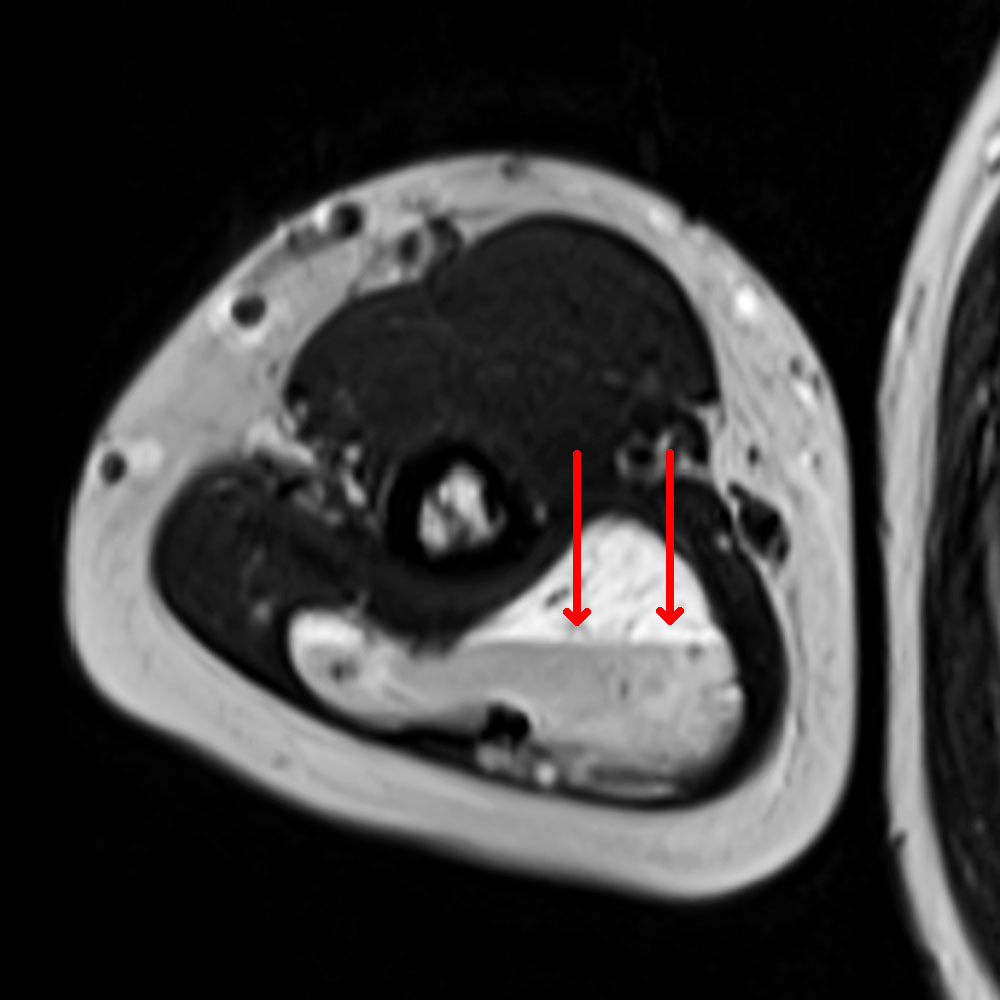

These clearly elevated D-dimer levels in patients with venous malformations, who may be otherwise quite healthy, do not occur in any other disease and are thus an important differential diagnostic component. Stagnant blood within the venous malformation results in classic fluid-fluid levels on imaging due to corpuscular blood components sinking with gravity in the absence of blood flow.

The normal organizing degradation of larger local thrombi or thrombophlebitis can lead to collagen deposition, which is palpable as a circumscribed induration over a longer period of time. If the thrombus then still cannot be completely degraded in the venous malformation, calcium deposition and increasing local, shell-like or popcorn-like calcification will occur over time. The final form is the calcified phlebolith as a round calcified lesion 1 cm in size on X-ray images of the venous malformation.